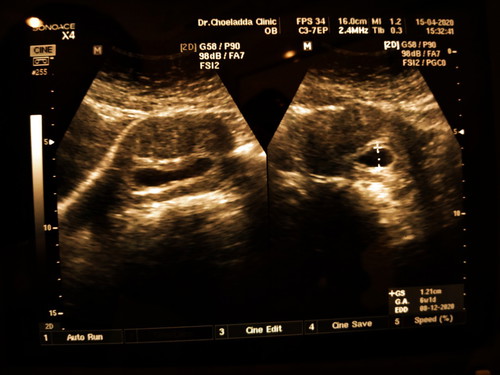

อัลตร้าซาวด์

เมื่อวานนี้ไปอัลตร้าซาวด์มาคะหมอบอกประมาน6สัปดาห์1วันแต่ไม่เห็นตัวน้องเรายังพอมีหวังไหมค่ะว่าน้องยังอยู่ แต่อาการของเราปกติค่ะเต้านมตึง ไม่มีเลือดออก ไม่ปวดท้อง